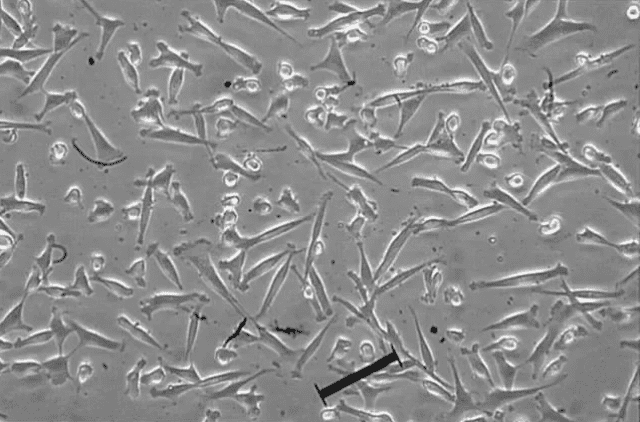

間充質(zhì)干細(xì)胞(mesenchymal stem cells,MSC)是干細(xì)胞的一種,因能分化為間質(zhì)組織而得名,具有亞全能分化潛能,在特定的體內(nèi)外環(huán)境下,能夠誘導(dǎo)分化成為多種組織細(xì)胞。間充質(zhì)干細(xì)胞具有干細(xì)胞的共性,即自我更新、多向分化和歸巢的能力。

具有很強(qiáng)的增殖能力和多向分化潛能,在體內(nèi)外合適的環(huán)境中能夠分化為肌細(xì)胞、肝細(xì)胞、成骨細(xì)胞、脂肪細(xì)胞、軟骨細(xì)胞、基質(zhì)細(xì)胞等細(xì)胞。

具有來源方便、易于分離、培養(yǎng)、擴(kuò)增和純化的優(yōu)點(diǎn),經(jīng)多次傳代和擴(kuò)增后仍具有干細(xì)胞的特性,不具有免疫排斥的特性。

間充質(zhì)干細(xì)胞易于體外擴(kuò)增,具有多種潛能。它們有望成為組織工程、細(xì)胞重編程和細(xì)胞轉(zhuǎn)分化的理想起始材料。